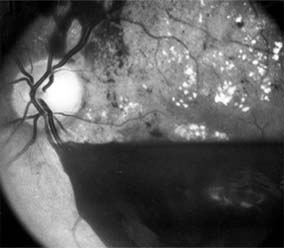

Chapter 10: Retina RETINAL VASCULAR DISEASES DIABETIC RETINOPATHY Diabetic retinopathy is one of the leading causes of blindness in the Western world. The view that chronic hyperglycemia of diabetes mellitus is the major determinant of diabetic retinopathy is supported by the observation that retinopathy in young people with type I (insulin-dependent) diabetes does not occur for at least 3-5 years after the onset of this systemic disease. Similar results have been obtained for type II (non-insulin-dependent) diabetes, but in such patients the time of onset and therefore the duration of disease are more difficult to determine precisely. It is recommended that patients with type I diabetes mellitus be referred for ophthalmologic examination within 3 years after diagnosis and reexamined on at least an annual basis. Type II diabetic patients should be referred for ophthalmologic examination at the time of diagnosis and reexamined at least annually. As diabetic retinopathy can become particularly aggressive during pregnancy, any diabetic woman who becomes pregnant should be examined by an ophthalmologist in the first trimester and at least every 3 months thereafter until parturition. In terms of both prognosis and treatment, it is useful to divide diabetic retinopathy into nonproliferative and proliferative categories. The prevalence of proliferative retinopathy in type I diabetics with 15 years of systemic disease is 50%. While the prevalence of proliferative disease at 15 years is much less in type II diabetics, the prevalence of macular edema as a function of the duration of systemic disease is the same in both groups. 1. NONPROLIFERATIVE DIABETIC RETINOPATHY Diabetic retinopathy is a progressive microangiopathy characterized by small vessel damage and occlusion. The earliest pathologic changes are thickening of the capillary endothelial basement membrane and reduction of the number of pericytes. Background diabetic retinopathy is a clinical reflection of the hyperpermeability and incompetence of involved vessels. The capillaries develop tiny dot-like outpouchings called microaneurysms, while the retinal veins become dilated and tortuous (Figure 10-20). Multiple hemorrhages may appear throughout different levels of the retina. Flame-shaped hemorrhages are so shaped because of their location within the horizontally oriented nerve fiber layer, while dot and blot hemorrhages are in the deeper retina, where cells and axons are vertically oriented. Macular edema is the most frequent cause of visual loss among patients with background diabetic retinopathy. The edema is caused primarily by a breakdown of the inner blood-retinal barrier at the level of the retinal capillary endothelium, allowing leakage of fluid and plasma constituents into the surrounding retina. The edema may be focal or diffuse and appears clinically as thickened, cloudy retina with associated microaneurysms and intraretinal exudate. Circinate zones of yellow, lipid-rich exudate may form around clusters of microaneurysms and are most frequently centered in the temporal portion of the macula. While the prevalence of macular edema is 10% in the diabetic population as a whole, there is a dramatic increase in prevalence in eyes with more severe retinopathy. With progressive microvascular occlusion, signs of increasing ischemia may be superimposed on the picture of background retinopathy and produce the clinical picture of preproliferative diabetic retinopathy. The most typical findings here are multiple cotton-wool spots, beading of the retinal veins, and irregular segmental dilation of the retinal capillary bed (intraretinal microvascular abnormalities). Closure of retinal capillaries surrounding the foveal avascular zone may cause significant ischemia, manifest clinically by the presence of large dark retinal hemorrhages and small thread-like macular arterioles. Eyes with macular edema and significant ischemia have a poorer visual prognosis-with or without laser treatment-than eyes with edema and relatively good perfusion. The visual and electrophysiologic dysfunctions associated with diabetes probably result from the local vascular abnormalities and the systemic metabolic effects of the disease to which the retina is subjected. A characteristic blue-yellow color vision abnormality develops, and hue discrimination may be impaired. Contrast sensitivity may be reduced in patients, even in the presence of normal visual acuity. Visual field testing may show relative scotomas corresponding to areas of retinal edema and nonperfusion, and abnormalities in dark adaptation have also been described. Electroretinographic abnormalities bear a relationship to the severity of retinopathy and may aid in predicting progression of retinopathy. Fluorescein angiography is invaluable in defining the microvascular abnormalities of diabetic retinopathy (Figures 10-21 and 10-22). Large filling defects of capillary beds-"capillary nonperfusion"-show the extent of retinal ischemia (Figure 10-23) and are usually most prominent in the midperiphery. The fluorescein leakage associated with retinal edema may assume the petaloid configuration of cystoid macular edema or may be diffuse. Other fluorescein abnormalities include vascular loops and intraretinal shunts. The focus of treatment in patients with nonproliferative diabetic retinopathy and no macular edema is treatment of hyperglycemia and intercurrent systemic disease. A controlled clinical trial has shown that aldose reductase inhibitor therapy does not prevent progression of diabetic retinopathy. Focal argon laser treatment of discrete points of retinal leakage in patients with clinically significant macular edema, principally defined as thickening of the retina at or within 500 2. PROLIFERATIVE DIABETIC RETINOPATHY The most severe ocular complications of diabetes mellitus are associated with proliferative diabetic retinopathy. Progressive retinal ischemia eventually stimulates the formation of delicate new vessels that leak serum proteins (and fluorescein) profusely. Neovascularization is frequently located on the surface of the disk and at the posterior edge of the peripheral zones of "nonperfusion" (Figures 10-24 and 10-25). Iris neovascularization, or rubeosis iridis, can also result. The fragile new vessels proliferate onto the posterior face of the vitreous and become elevated once the vitreous starts to contract away from the retina. If the vessels bleed (Figure 10-26), massive vitreous hemorrhage may cause sudden visual loss. Eyes in which posterior vitreous detachment is complete are at less risk of developing neovascularization and vitreous hemorrhage. In eyes with proliferative diabetic retinopathy and persistent vitreoretinal adhesions, elevated neovascular fronds may undergo fibrous change and form tight fibrovascular bands that tug on the retina and exert continued vitreous contraction. This can cause either a progressive traction retinal detachment or, if a retinal tear is produced, rhegmatogenous retinal detachment. The retinal detachment may be heralded or concealed by vitreous hemorrhage. When vitreous contraction is complete in these eyes, proliferative retinopathy tends to enter the burned-out or "involutional" stage. Treatment Argon laser panretinal photocoagulation is usually indicated in proliferative diabetic retinopathy. Patients at greatest risk of significant visual loss are those with preretinal or vitreous hemorrhage or neovascularization of the disk. Panretinal photocoagulation can significantly reduce the chance of massive vitreous hemorrhage and retinal detachment in these patients by causing the regression and, in some cases, the disappearance of new vessels. The technique involves scattering up to several thousand regularly spaced laser burns throughout the retina, sparing the central region bordered by the disk and the major temporal vascular arcades (Chapter 24). Although the mechanism is not precisely understood, panretinal photocoagulation presumably works by reducing the angiogenic stimulus from ischemic retina. The role of vitreoretinal surgery in proliferative diabetic eye disease continues to evolve. Conservative management of monocular vision impairing diabetic vitreous hemorrhage in the binocular patient had been to allow spontaneous resolution over the course of several months. The results of a 4-year study designed to assess the role of early vitrectomy for severe vitreous hemorrhage and proliferative diabetic retinopathy support this surgery as a means by which good vision may be restored or maintained. The role of vitreoretinal surgery in the treatment of diabetic traction retinal detachment is described elsewhere in this chapter. CENTRAL RETINAL ARTERY OCCLUSION The patient with central retinal artery occlusion routinely relates a history of painless catastrophic visual loss occurring over a period of seconds; antecedent transient visual loss (amaurosis fugax) may be reported. The visual acuity ranges between counting fingers and light perception in 90% of eyes at the time of initial examination. An afferent pupillary defect can appear within seconds after retinal arterial obstruction, preceding the fundus abnormalities by an hour. Ophthalmoscopically, the superficial retina becomes opacified except in the foveola, where a cherry-red spot is evident (Figure 10-27). The cherry-red spot is pigment of the choroid and retinal pigment epithelium viewed through the extremely thin overlying foveolar retina and contrasted with the thicker and translucent perifoveolar retina. Twenty-five percent of eyes with central retinal artery occlusion have cilioretinal arteries that spare macular retina and may preserve some central visual acuity. Clinically, the retinal opacification resolves within 4-6 weeks, leaving a pale optic disk as the major ocular finding. In older patients, giant cell arteritis must be excluded and if necessary treated immediately with high doses of systemic corticosteroids. Other causes of central retinal artery occlusion are arteriosclerosis and emboli from carotid or cardiac sources. These are discussed further in Chapter 15. Treatment Because irreversible retinal damage has been shown to occur after 90 minutes of complete central retinal artery occlusion in the subhuman primate model, precious little time is available in which to begin therapy. Anterior chamber paracentesis can be employed in order to decrease intraocular pressure and increase retinal perfusion. This is particularly indicated in embolic central retinal artery occlusion. Intravenous acetazolamide has been used to decrease intraocular pressure, and an inhaled oxygen-carbon dioxide mixture has been employed to induce retinal vasodilation and increase the PO2 at the retinal surface. Direct infusion of a thrombolytic agent into the ophthalmic artery can result in recovery of vision. It must be performed within 8 hours after onset of the central retinal artery occlusion, requires specific radiologic expertise, and there is a risk of cerebral infarction. Systemic anticoagulants are generally not employed. BRANCH RETINAL ARTERY OCCLUSION Branch retinal artery occlusion usually presents with sudden loss of visual field and with reduction in visual acuity if the fovea is involved. Fundus signs of retinal edema with associated cotton-wool spots are limited to the area of retina supplied by the occluded vessel. Embolic causes are proportionately more common than in central retinal artery occlusion, and emboli are frequently identified on clinical examination (see Chapter 15). Migraine, oral contraceptive use, and vasculitis must also be considered. CENTRAL RETINAL VEIN OCCLUSION Central retinal vein occlusion is a common and easily diagnosed retinal vascular disorder with potentially blinding complications. The patient presents with sudden painless loss of vision. The clinical appearance varies from a few small scattered retinal hemorrhages and cotton-wool spots (Figure 10-28) to a marked hemorrhagic appearance with both deep and superficial retinal hemorrhage, which may rarely break through into the vitreous cavity. Most patients who develop the disease are over 50 years of age, and more than half have associated cardiovascular disease. Predisposing factors and their investigation are discussed in Chapter 15. Chronic open-angle glaucoma should always be excluded (see Chapter 11). The two major complications associated with central retinal vein occlusion are reduced vision from macular edema and neovascular glaucoma secondary to iris neovascularization. Macular dysfunction occurs in almost all eyes with central vein occlusion. Although some eyes will show spontaneous improvement, most eyes will have persistent decreased central vision as a result of chronic macular edema. Nearly one-third of eyes with central retinal vein occlusion show significant retinal capillary nonperfusion on fluorescein angiography; one-half of these eyes will develop neovascular glaucoma. Treatment Careful follow-up evaluation is warranted, and prompt panretinal laser photocoagulation is recommended for eyes that develop anterior segment neovascularization. No treatment for macular edema, including grid pattern photocoagulation, has proved effective to date. BRANCH RETINAL VEIN OCCLUSION Branch retinal vein occlusion presents as sudden unilateral vision loss with segmentally distributed intraretinal hemorrhage. The vein occlusion always occurs at the site of an arteriovenous crossing (Figure 10-29), and retinal neovascularization may develop if the occlusion produces an area of retinal capillary nonperfusion that is more than 5 disk diameters in area. Sight-threatening complications of the disease are macular edema, macular ischemia, and vitreous hemorrhage from retinal neovascularization. Treatment Once peripheral retinal neovascularization has developed, sectoral laser retinal photocoagulation to the area of ischemic retina reduces the risk of vitreous hemorrhage by one-half. When vision loss due to macular edema persists for several months without spontaneous improvement, grid pattern argon laser macular photocoagulation may be indicated. Anticoagulant therapy has not been shown to be beneficial in either the prevention or the management of branch retinal vein occlusion. Investigation for an underlying systemic cause is discussed in Chapter 15. Important associated ocular diseases are chronic open-angle glaucoma and uveitis secondary to Behçet's syndrome. RETINAL ARTERIAL MACROANEURYSM Retinal macroaneurysms are fusiform or round dilations of the retinal arterioles occurring within the first three orders of arteriolar bifurcation. Most cases are unilateral, and the superotemporal artery is the most commonly involved vessel. Two-thirds of patients have associated systemic arterial hypertension. The most common clinical symptom is loss of central vision as a result of retinal edema, exudation, or hemorrhage. Macroaneurysms may bleed into the subretinal space, into the retina, beneath the internal limiting membrane, or into the vitreous; the "hourglass" hemorrhage is typical and is due to bleeding beneath and anterior to the retina. Although no clear indication for treatment with laser photocoagulation has been established, laser treatment of the macroaneurysm should be considered if lipid exudate coming from it threatens the fovea. PREVIOUS | NEXT Page: 1 | 2 | 3 | 4 | 5 | 6 | 7 | 8 | 9 10.1036/1535-8860.ch10 |